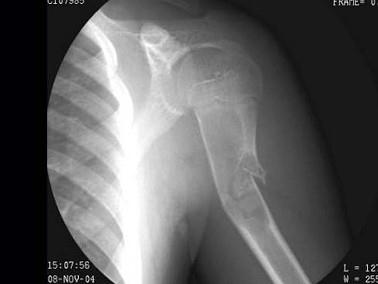

问题 5岁男性患者,外伤后致使左肩关节疼痛伴关节活动障碍1小时,X线检查如图所示,最可能的诊断是: ( )

选项 A、左肱骨上段嗜酸性肉芽肿伴病理性骨折 B、以上都不正确 C、肱骨骨纤伴病理性骨折 D、肱骨上段骨囊肿伴病理性骨折 E、左肱骨上段骨折

答案 D